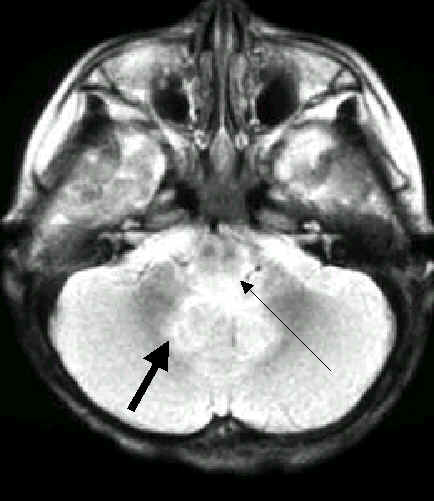

2歲女孩,手足口疾病合併腦炎

腦炎侵犯

中腦的中央及後面

橋腦的後及腦齒狀核

腦炎更往下

侵犯脊髓

中腦的中央及橋腦、延腦的後面及小腦齒狀核,

更往下侵犯脊髓